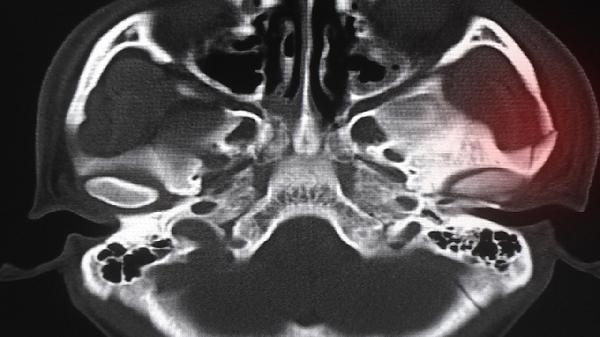

骨折部位血液供应不足是导致骨不愈合的常见原因。骨骼愈合需要充足的血液输送氧气和营养物质,当骨折处血管损伤严重或局部血液循环障碍时,成骨细胞活性降低,影响骨痂形成。中医认为这与"瘀血阻滞"有关,可通过活血化瘀类中药如三七、红花配合针灸改善微循环。

开放性骨折或术后感染会破坏骨愈合环境。细菌产生的毒素和炎症反应会抑制成骨细胞分化,导致骨折线持续存在。临床表现为局部红肿热痛、脓性分泌物,需进行细菌培养后针对性使用抗生素。中医辨证多属"热毒炽盛",可配合清热解毒方剂如五味消毒饮。

骨折端异常活动会反复损伤新生毛细血管和骨痂。外固定支架松动、内固定物失效或过早负重都会造成机械性不稳定,使纤维组织取代骨组织填充骨折间隙。需通过影像学评估固定效果,必要时手术调整固定方式。中医强调"动静结合",在稳定固定基础上配合轻柔的导引术。